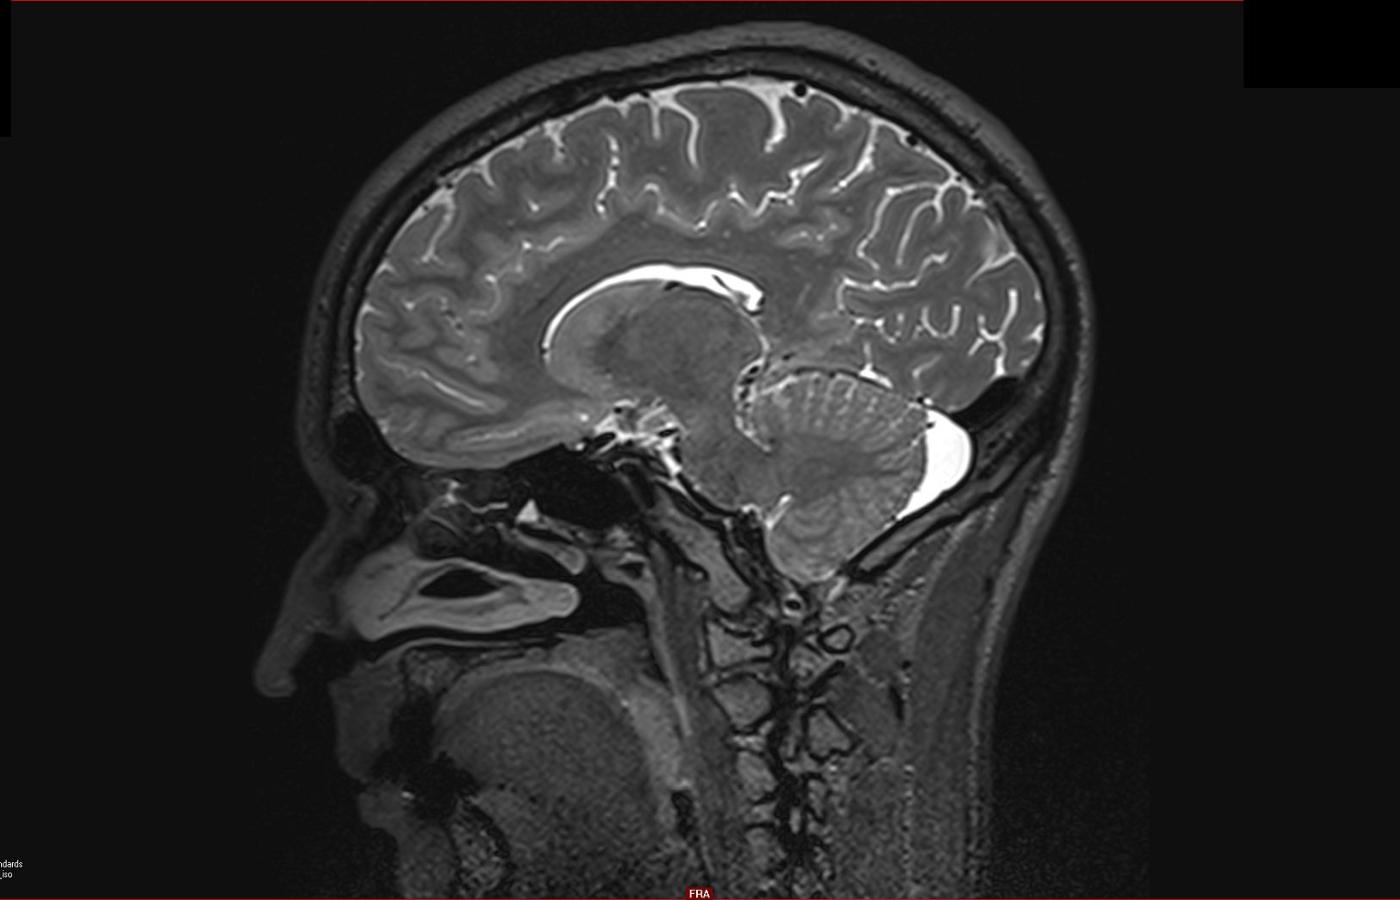

Ludzki mózg liczy ok. 86 mld neuronów i 100 bln synaps (miejsc, w których komórki nerwowe przekazują sobie informacje).DerCosmo/Wikipedia Ludzki mózg liczy ok. 86 mld neuronów i 100 bln synaps (miejsc, w których komórki nerwowe przekazują sobie informacje).